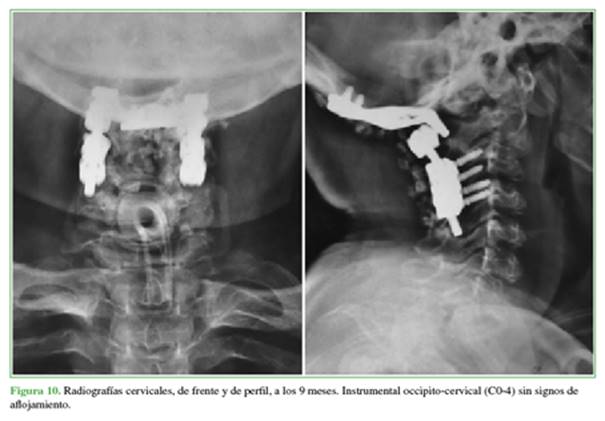

Cuando se redactó este artículo (a los 18 meses de la cirugía), la paciente continuaba con traqueotomía, deambulaba sin asistencia dentro del domicilio y con asistencia fuera del hogar, las parestesias y la cervicalgia habían mejorado (Figura 9), y la distancia de marcha preclaudicación había aumentado. No se observaron signos de aflojamiento en las últimas radiografías (Figura 10).